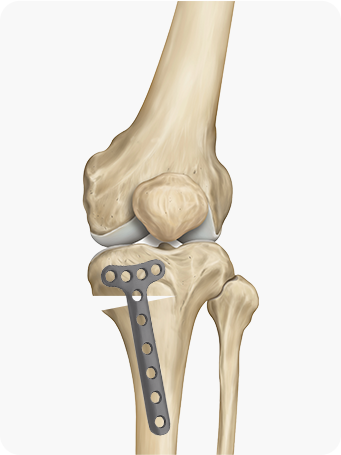

종아리뼈 일부를 절골한 후, 수술 기구를 이용하여 필요한 각도만큼 뼈를 벌려

금속판과 나사를 이용하여 고정합니다.

해골 이미지

경골을 절골하여 원하는 각도로 벌려 무게 중심이

바깥쪽으로 옮겨지도록 교정

합니다. 절골한 부위를

금속판과 나사로 고정해 뼈가 안정적으로 붙도록 합니다.